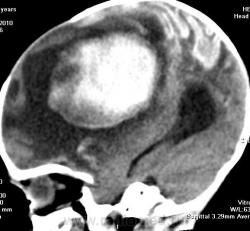

Я думаю, это больше похоже на кровоизлияние - неоднородная структура с гиперденсным компонентом. Плюс ко всему - клиника, судя по всему, с острым началом. Опухоли быстро не растут.

Смущает то, что кровоизлияние как бы в капсуле. А что с извилинами? Пропитывание кровью?

Паразитарная киста - это эхинококк? Образование имеет плотность свежей крови, так что кровоизлияние не вызывает сомнений. Но вот возможно кровоизлияние в опухоль или в результате какой-либо сосудистой патологии, например, ангиоматоза Штурге-Вебера. Насчет течения родов попробую уточнить.

Светлые участки 70 ед Н - плотности крови.

А ведь кровоизлияние есть субарохноидально.

Денди Уокер? Не думаю, хотя надо посмотреть аксиалы ниже уровня намёта. А пока явно вижу признаки Sturge-Weber syndrome - encephalotrigeminal angiomatosis синдром со всеми вытекающими.